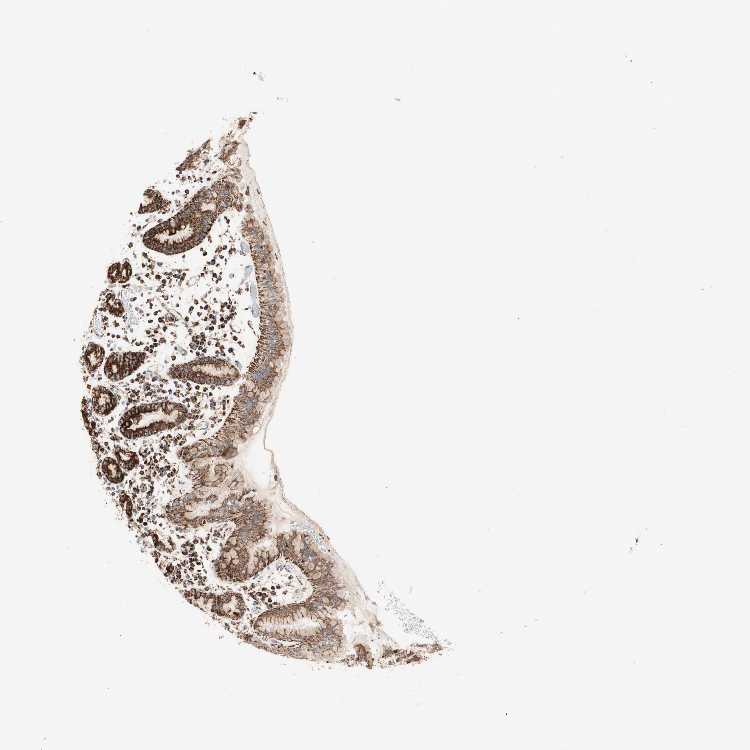

STOMACH 1 - Antibody stainingi

Antibody staining in the annotated cell types in the current human tissue is reported as not detected, low, medium, or high, based on conventional immunohistochemistry profiling in selected tissues. This score is based on the combination of the staining intensity and fraction of stained cells.

Each image is clickable and will lead to virtual microscopy that enables deeper exploration of all samples and also displays staining intensity scores, fraction scores and subcellular localization as well as patient and tissue information for each sample.

Antibody HPA011562Antibody CAB005585

Glandular cells HighHigh